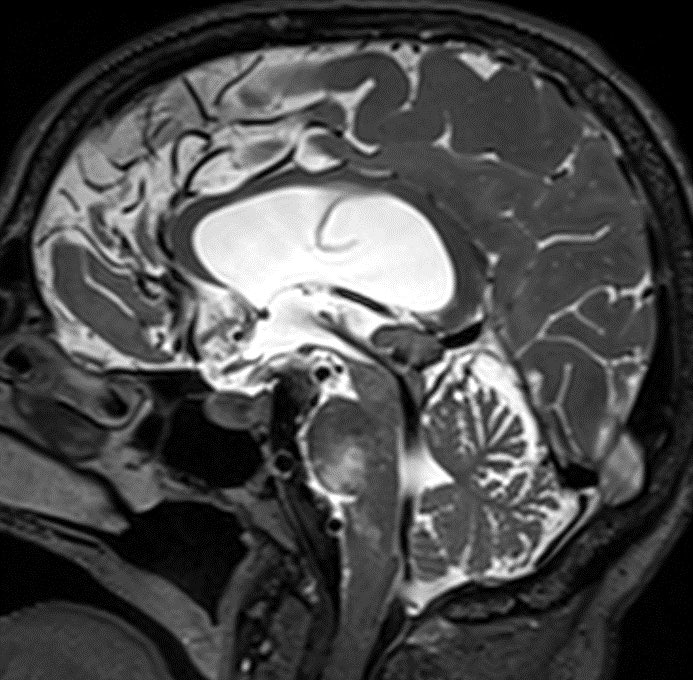

80 y/o patient presenting w/ headache is found to have a pineal mass and hydrocephalus. What is the most likely diagnosis and cause of the hydrocephalus?